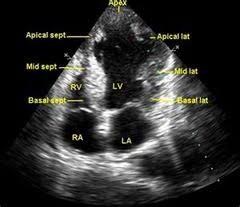

심장 초음파는 인체에 무해한 초음파를 이용해 실시간으로 이러한 심장의 움직이는 모습을 관찰할 수 있고 심장의 움직임과 구조, 혈류의 흐름, 판막의 이상 유무 등을 비침습적으로 관찰할 수 있는 검사법이라고 한다. 대부분의 심장 질환에 필수적인 검사며, 많은 심장질환에서 높은 정확도를 가진다고 한다.

심장 초음파를 통해 심장근육의 손상여부나 좌심실 벽의 두께 등을 관찰해 협심증, 심근경색 등을 알아낼 수 있다고 한다.